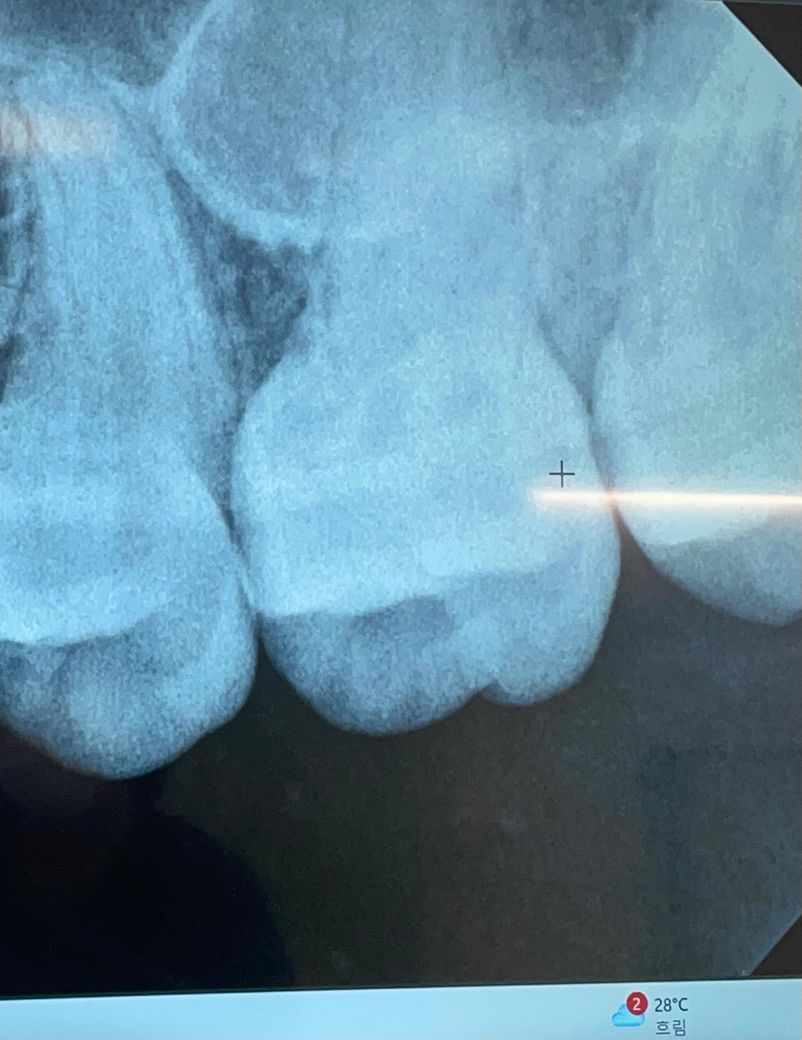

치아 인접면 충치 봐주세요 !! 치아사이충치

치과에서 따로 언급은 안하셨는데 사진의 치아 사이도 충치 있는 건가요..? 충치 없어도 엑스레이 상에는 원래 저런건가요?…….

엑스레이 상으로는 치아 사이에 충치가 없어도 촬영각도나 치아에 따라서 충치치럼 보이는 경우도 있습니다.

사진만으로 판별하기에는 어려움이 있지만 심하진 않고 초기 우식 정도는 가능성이 있어보입니다.

사진으로 봤을 경우 방사선으로 약간 음영에 보이긴 합니다. 하지만 충치가 있다고 확신을 할 순 없으며 육안상 확인이 필요할 것으로 생각됩니다.

자세한 확인을 위해서 치과에서 진료를 받아보는 것을 권유드립니다.